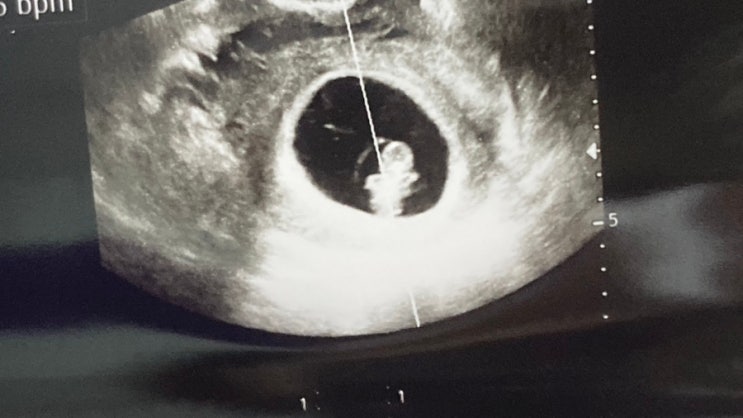

임신초기 증상 기록 두번째 (8주~11주) 입덧 시작

안녕하세요~! 임밍아웃과 임신극초기 기간을 지나서 진짜 초기 기록을 해보려고 합니다. 제일 먼저 여름휴...

임밍아웃과 임신초기 기록 (4주~7주) 완전 초기 증상 (사진x)

안녕하세요~ 저 둘째 임신했답니다~!! 워낙 노산인 저라 주변에 임밍아웃도 20주에, 지금은 25주차를 보내...